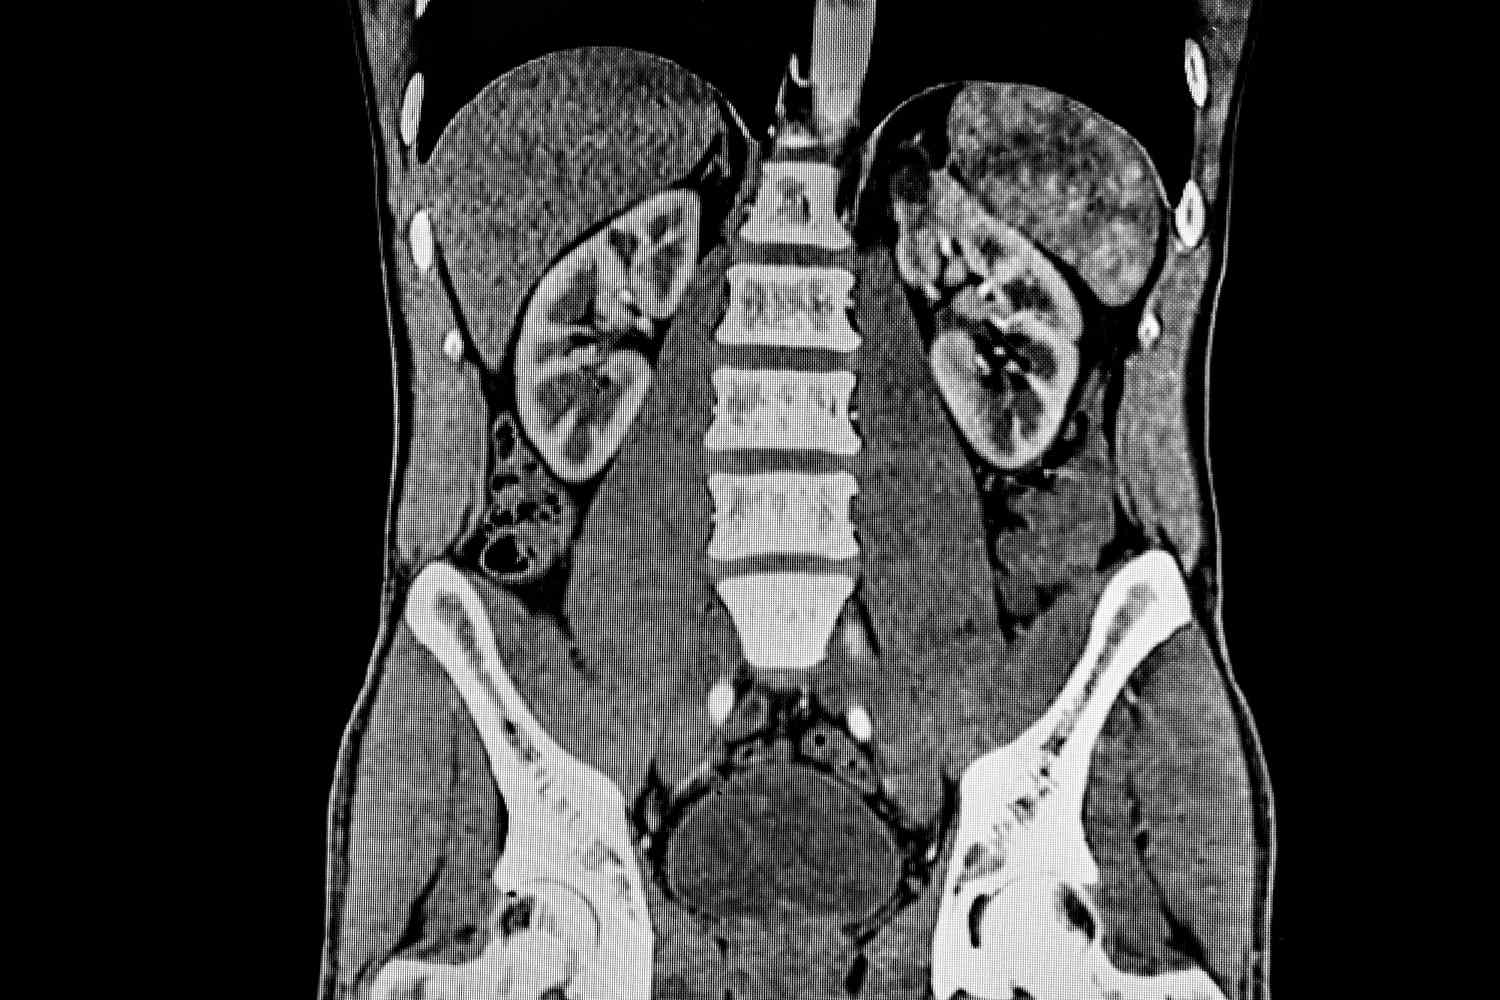

Computed tomography (CT) of the abdomen and pelvis is a diagnostic imaging test designed to provide detailed images of the organs and structures within these regions. This scan is used for a variety of reasons, including the detection of kidney stones, the investigation of unexplained abdominal pain or nausea/vomiting, and the diagnosis of conditions such as appendicitis and diverticulitis. Additionally, it plays a crucial role in assessing various cancers affecting the organs in the abdomen and pelvis, such as the liver, pancreas, and reproductive organs.

Abdominal and pelvic CT scans are commonly used to diagnose a variety of conditions affecting the abdomen and pelvis. This procedure is crucial for identifying the causes of abdominal or pelvic pain and for assessing diseases of the internal organs, small bowel, and colon. It is frequently utilized to detect infections such as appendicitis, diverticulitis, pyelonephritis, and abscesses, which are infected fluid collections.

Additionally, CT scans are important for diagnosing inflammatory bowel diseases like ulcerative colitis and Crohn's disease, as well as pancreatitis. They are also instrumental in identifying and tracking cancers affecting organs such as the liver, bowel, kidneys, pancreas, adrenal glands, uterus, ovaries, and bladder.

Furthermore, these scans are used to evaluate the spread of cancers from other body parts, including lung and breast cancer, to the abdomen and pelvis. Other uses include locating kidney and bladder stones, detecting abdominal aortic aneurysms (AAA), and assessing injuries to abdominal organs like the spleen, liver, and kidneys in cases of trauma. Beyond diagnosis, abdominal and pelvic CT scans help guide biopsies, abscess drainages, and minimally invasive tumor treatments. They are also employed to plan and assess the outcomes of surgeries, such as organ transplants, and to stage cancers, plan radiation treatments, and monitor responses to chemotherapy. This comprehensive explanation ensures an accurate and plagiarism-free overview of the common uses of abdominal and pelvic CT scans.